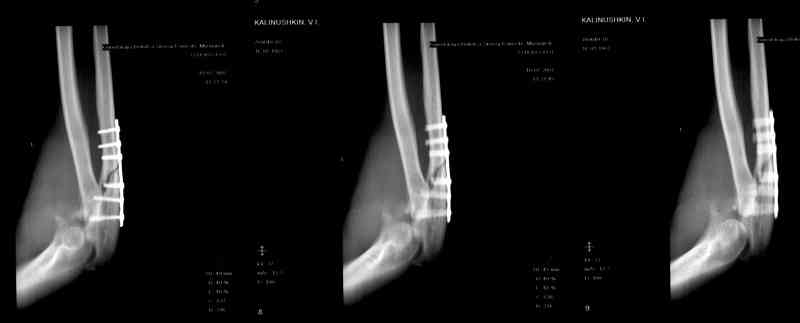

Re: Несросшийся перелом локтевой кости, подвывих предплечья кзади.Перелом венечного отростка. Состояние после резекции головки лучевой. Травма 4 мес. назад.

Больной наблюдался в поликлинике,к нам попал

через 3 мес. Отмечается контрактура локтевого сустава, сгибание/разгибание 30/0/0.

МРТ у нас нет, сделаны томограммы.